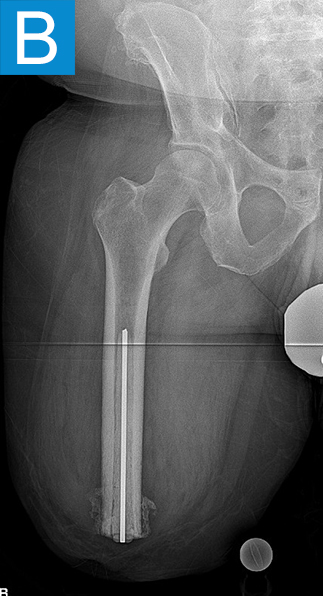

Standing radiographs showed periosteal reaction to the distal femoral isthmus, and given the chronicity of his infections the decision was made to stage the transfemoral amputation and osseointegration implant insertion (Figure 1b). During the amputation, the tibial and peroneal nerves underwent targeted muscle reinnervation to the motor branches of the medial and lateral hamstrings, respectively. Cement mixed with tobramycin and vancomycin was placed in the femoral canal, and the remaining musculature was purse stringed around the residual femur. His proximal cultures were negative, and so no further antibiotic treatment was given. Approximately 8 weeks later, the antibiotic spacer was removed and a press fit femoral osseointegration implant was placed in a percutaneous procedure (Figure 2a). Cultures of the canal remained negative.

Figure 1. Preoperative X-rays show (A) static cement spacer on antibiotic suppression and (B) an antibiotic cement spacer in the residual femur.